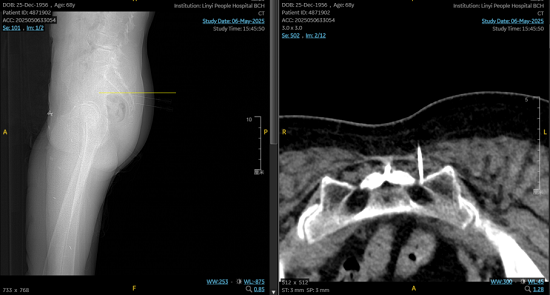

临沂市人民医院疼痛科王飞主任团队采用的CT引导下骶神经脉冲射频术,通过三维成像精确定位S3神经孔,将射频电极误差控制在1毫米内,利用42℃脉冲电流调节异常神经信号。该技术具有三大临床优势,一是微创精准:CT可视化引导避免血管脏器损伤,二是快速起效:术后15分钟疼痛评分从9-10分骤降至1-2分,三是持久镇痛:联合奇神经节调节技术改善局部血供。